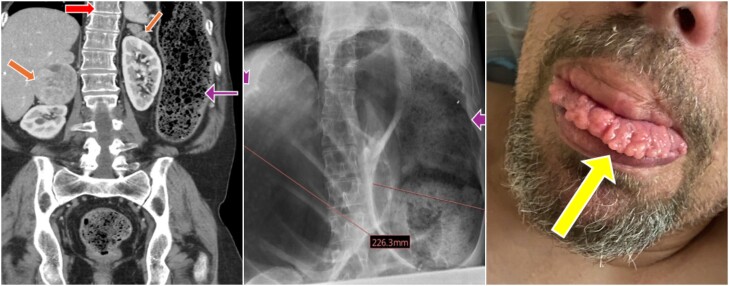

3 in 1: Manifestations of Multiple Endocrine Neoplasia Type 2B on Imaging.

3 / 1:多发性内分泌瘤2B型的影像学表现。